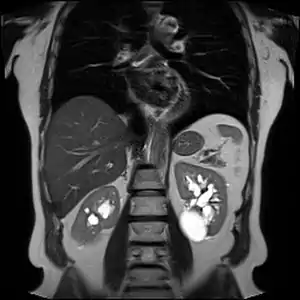

![]() | |

| Renal cyst of the left kidney (hyperintense area) as shown on MRI. | |

Advanced polycystic kidney disease with multiple cysts.[8]